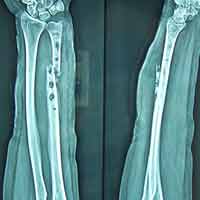

Case:6 Segmental Comminuted Fracture Radius

Patient, aged 75 years during morning walk tripped & had a fall following which he sustained injury to the left forearm. Closed reduction & interval fixation with Intra-medullary TEN nails was done in radius & ulna. Now he has full supination & pronation function of forearm.

Pre-Op

Post-Op